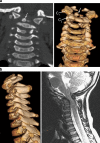

Background: The embryology of the bony craniovertebral junction (CVJ) is reviewed with the purpose of explaining the genesis and unusual configurations of the numerous congenital malformations in this region. Functionally, the bony CVJ can be divided into a central pillar consisting of the basiocciput and dental pivot and a two-tiered ring revolving round the central pivot, comprising the foramen magnum rim and occipital condyles above and the atlantal ring below. Embryologically, the central pillar and the surrounding rings descend from different primordia, and accordingly, developmental anomalies at the CVJ can also be segregated into those affecting the central pillar and those affecting the surrounding rings, respectively.